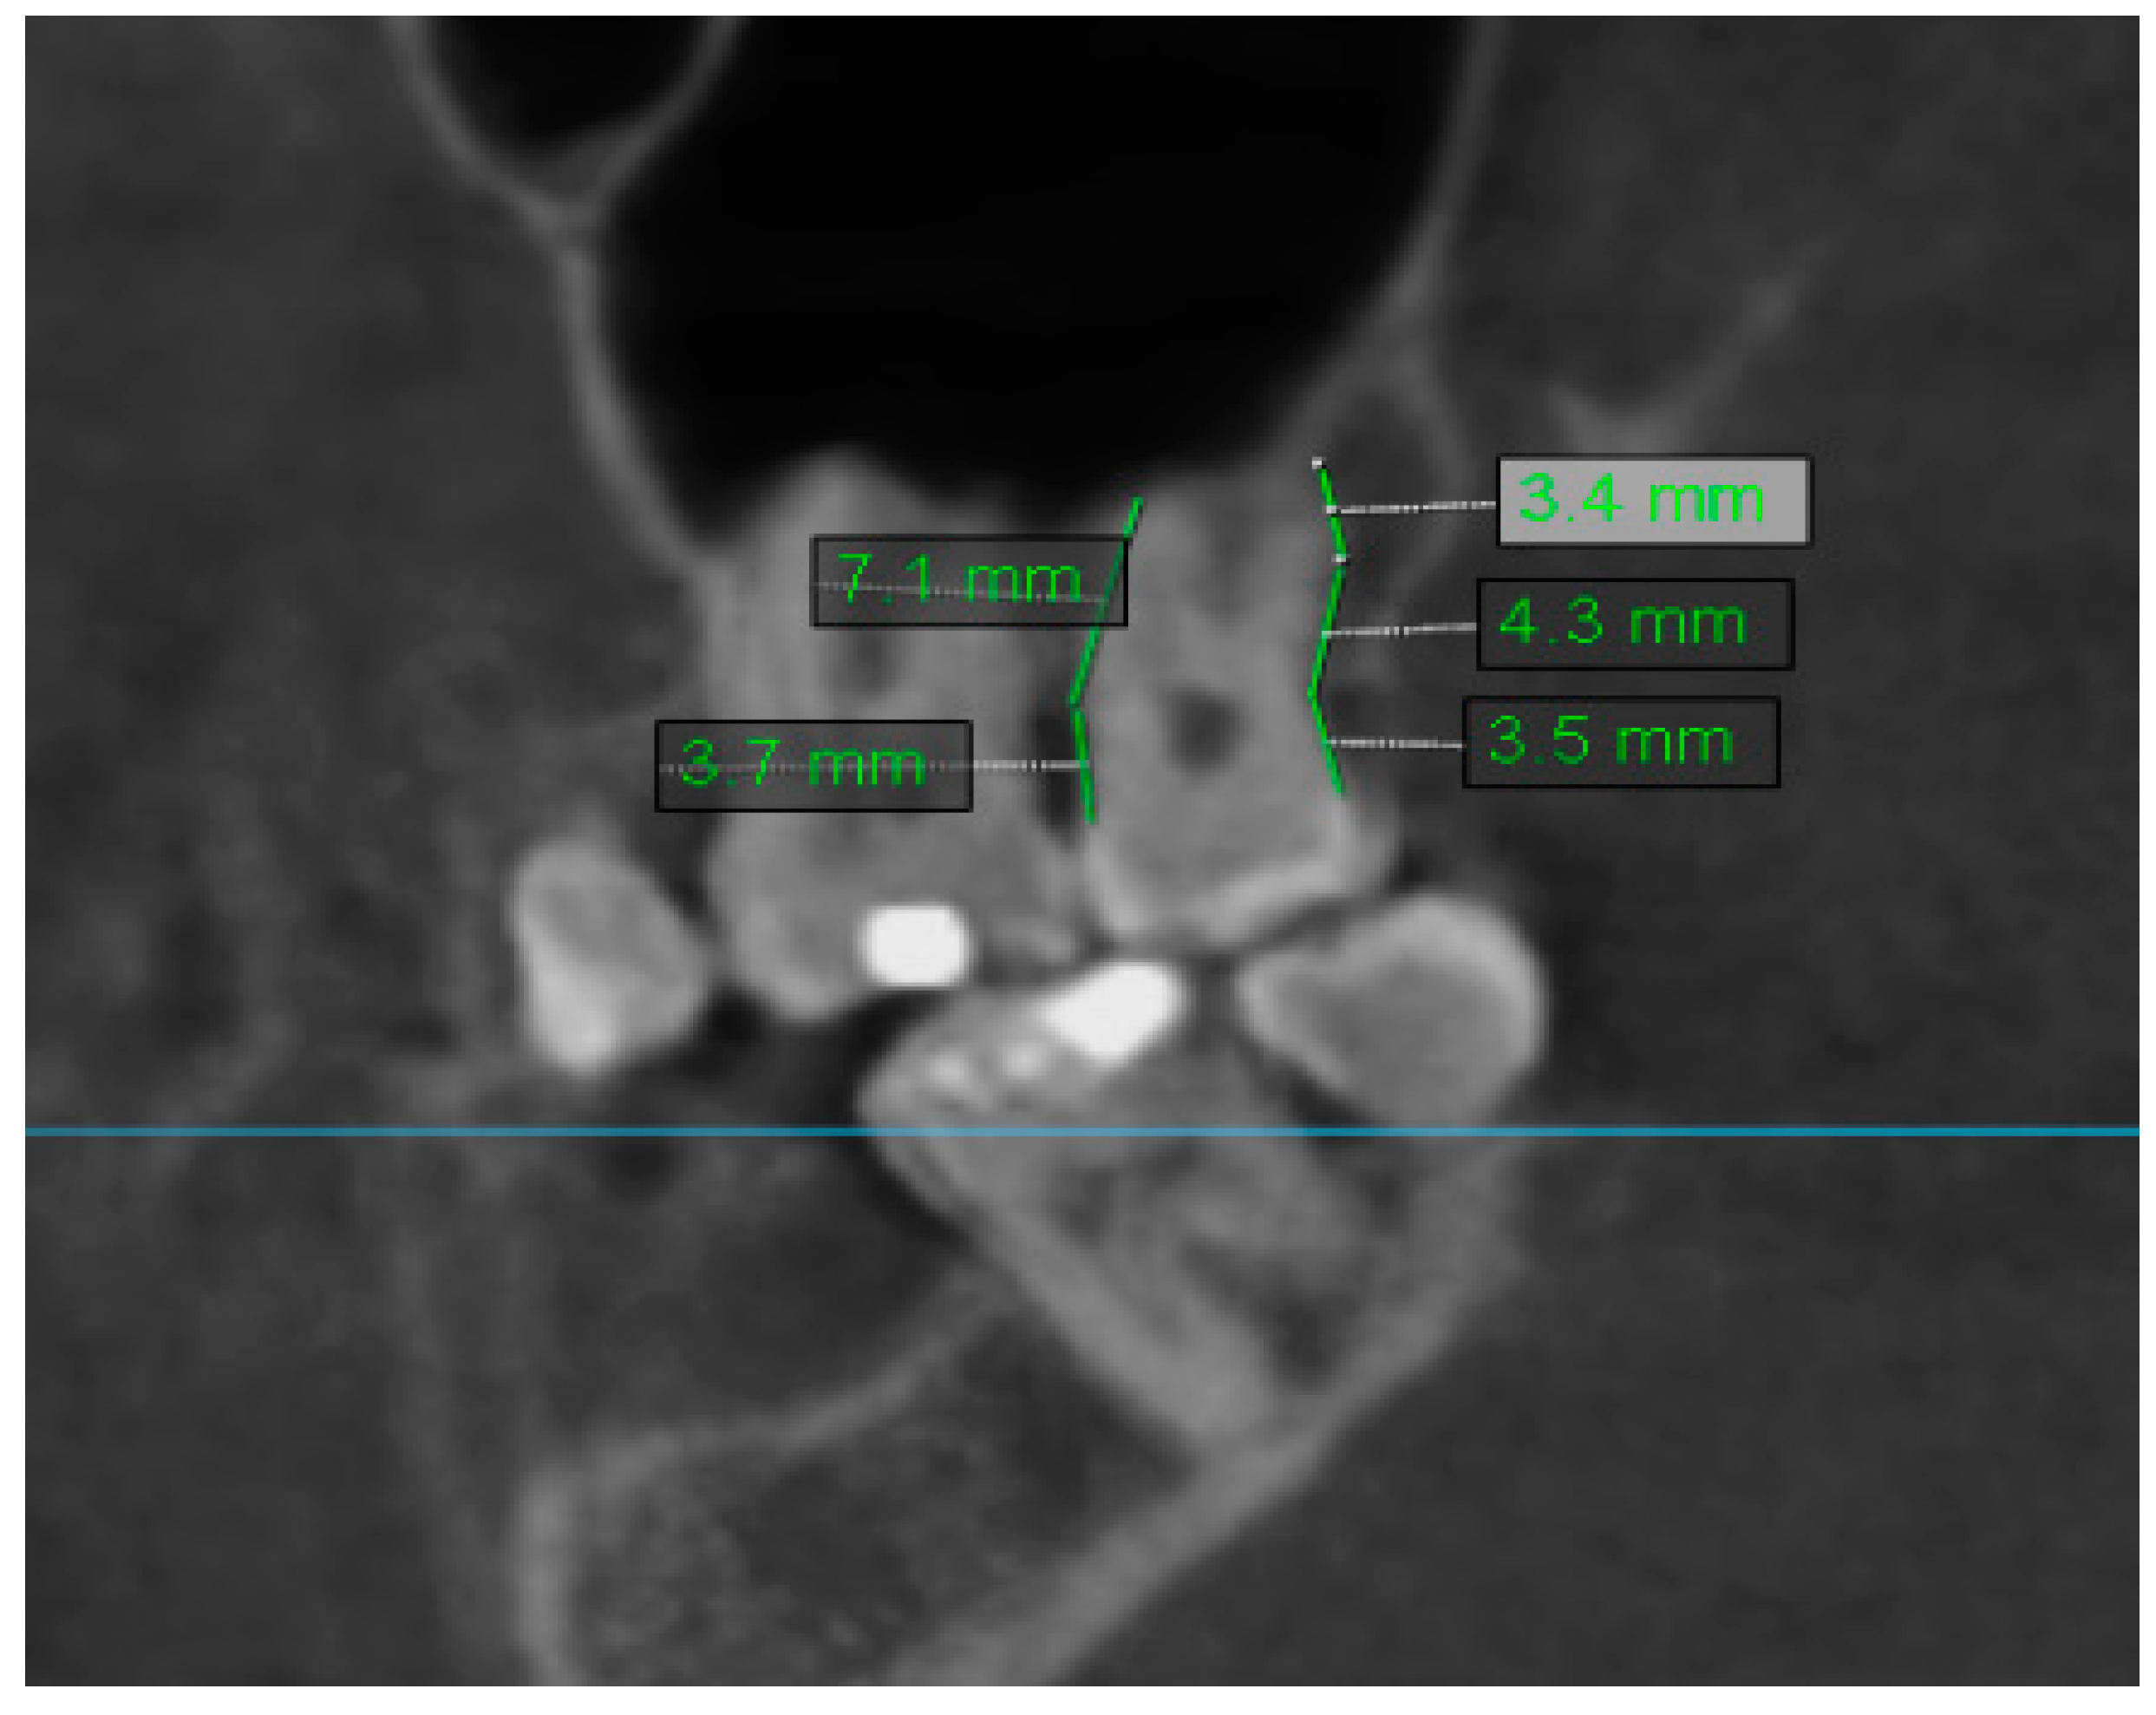

2.2. Assessment of Anatomic Relation between Teeth and Maxillary Sinus

2.3. Assessment of Periodontal Bone Loss